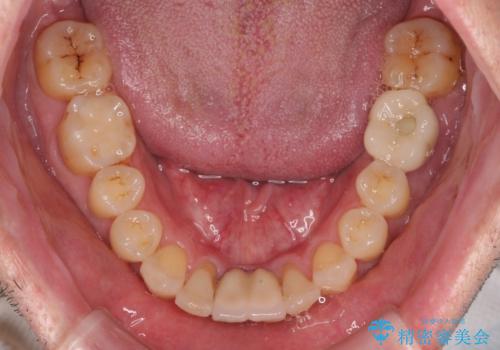

矯正治療を行いながら、欠損部はインプラントによる補綴治療を希望されたため、補助装置を用いたワイヤー矯正によりスペースを確保しながら歯列を整え、適宜インプラントを埋入していくこととしました。

下顎前歯にインプラントを2本埋入するのは非常に困難であり、どうしても歯肉位置に土台の金属色が見えてしまう仕上がりとなりました。無理をせずに1本のみの埋入とするか、ブリッジを提案しましたが、患者様の強い希望により、2本埋入することとなり、大変満足していただけました。